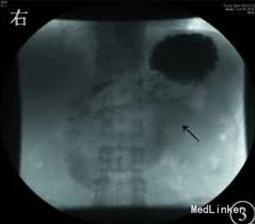

予加强静脉营养、内科保守治疗,无好转,再行上消化道碘油造影示十二指肠水平部狭窄,造影剂无法通过,采取俯卧位后造影剂可通过,但十二指肠升部与空肠交界处狭窄,造影剂无法通过。考虑存在十二指肠与空肠交界处病变,恶性肿瘤不能排除,遂决定手术探查。术中在十二指肠升部与空肠交界处可见一肿瘤,最大径约为3cm,累及浆膜,相应肠管狭窄梗阻,系膜可见肿大淋巴结,另可见肠系膜上血管与腹主动脉间脂肪组织减少,十二指肠水平部部分被压迫,探查其余小肠及结肠未见异常,肝脏、盆腔、腹主动脉旁未见明显转移,腹腔未见腹水。术后病理诊断示小肠中至低分化腺癌,侵及浆膜外脂肪组织,脉管中见癌栓。上、下切端均未见癌组织累及,周围脂肪组织中的16枚淋巴结中5枚见转移性癌组织,另见癌结节2枚。免疫组织化学检查示,细胞角蛋白7阴性,细胞角蛋白20、CEA 、绒毛蛋白、细胞角蛋白19、CA19-9和 CD34血管阳性,Ki‐67抗原约85%阳性。术后患者恢复良好,无恶心、呕吐,出院后胃纳正常。1个月后复诊体质量增加约5 kg。